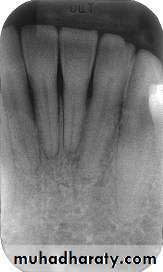

Mandibular incisor region

Mandibular canine region